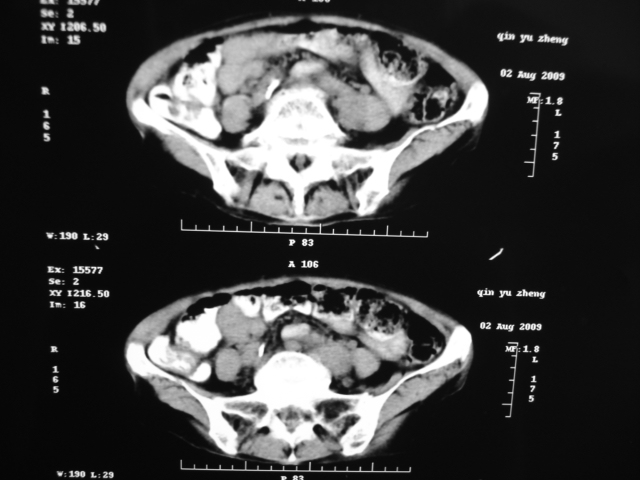

同事奶奶,73岁,腹痛一年,夜晚较重,潜血+++,拒绝增强,考虑左肾ca并腹膜后转移;请各位老师帮忙看看,谢谢!

左肾癌侵及输尿管上段,腹膜后多发淋巴结转移,脾脏钙化灶。至于潜血+++,要考虑消化道病变,本次ct片肠腔未见明显异常。

查查一胸部,不除外肺癌伴左侧肾上腺,腹膜后淋巴结及左肾转移.

定位像见上肺野也很糟糕,支持7楼。